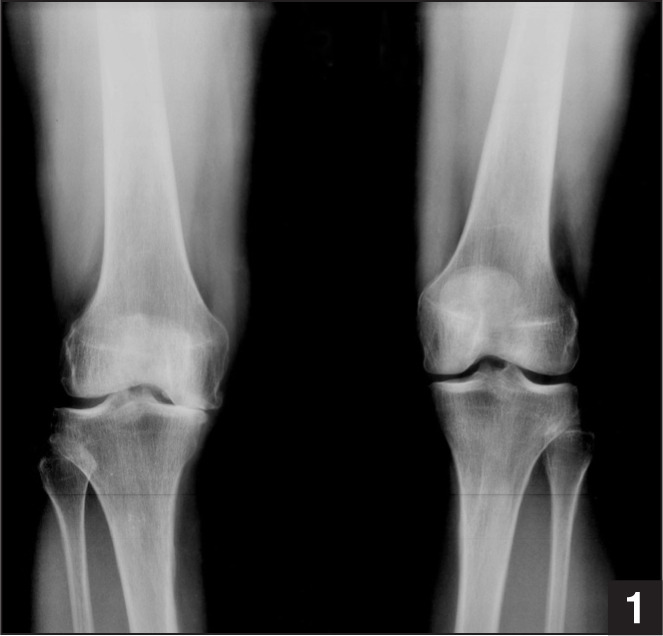

What is this depicting and what are your considerations when measuring the deformity?

CORA - center of rotation of angulation

What is your appraoch to this patient?

Technical goals of TKA

Important considerations for planning your TKA cuts

Femur

Tibia